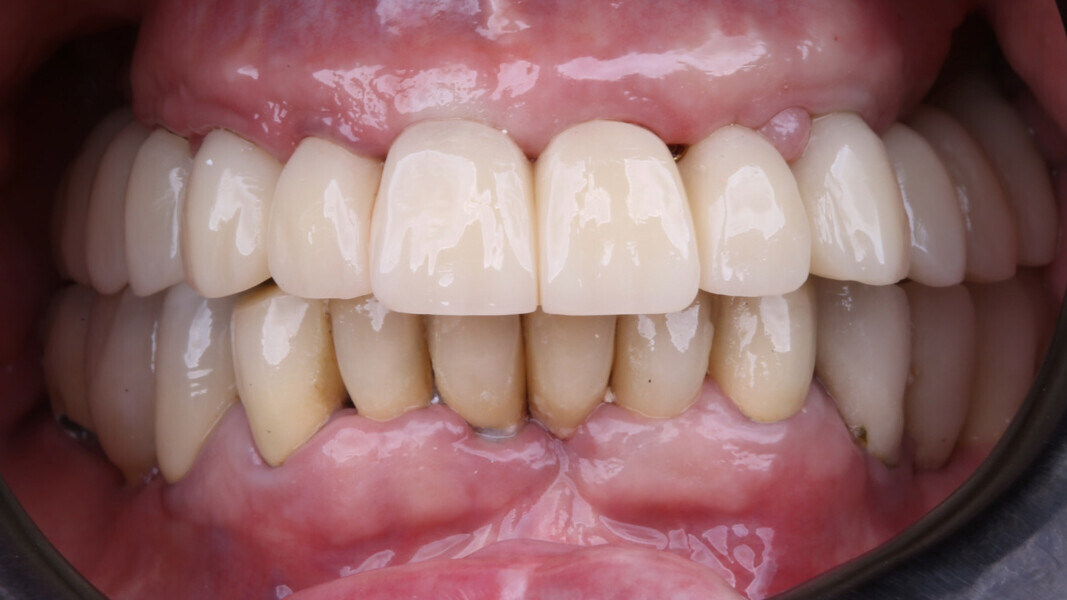

At the final appointment, the definitive hybrid screw-retained prosthesis was delivered. The definitive prosthesis consisted of a CAD/CAM titanium framework screwed on to all of the implants and three monolithic zirconia prosthetic segments bonded on top (Figs. 18a–c). The occlusion was evaluated, and the patient was enrolled in a four-month maintenance programme. At the last follow-up (one year after implant placement), all of the implants were successful and the patient was fully satisfied with the new prosthesis (Figs. 19–22).